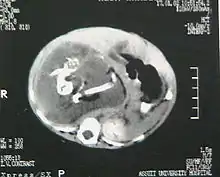

Fetus in fetu (or foetus in foetu) is a developmental abnormality in which a mass of tissue resembling a fetus forms inside the body. An early example of the phenomenon was described in 1808 by George William Young.[1]

There are two theories of origin concerning "fetus in fetu". One theory is that the mass begins as a normal fetus but becomes enveloped inside its twin.[2] The other theory is that the mass is a highly developed teratoma. "Fetus in fetu" is estimated to occur in 1 in 500,000 live births.[3]

A fetus in fetu can be considered alive, but only in the sense that its component tissues have not yet died or been eliminated. Thus, the life of a fetus in fetu is akin to that of a tumor in that its cells remain viable by way of normal metabolic activity. However, without the gestational conditions in utero with the amnion and placenta, a fetus in fetu can develop into, at best, an especially well differentiated teratoma; or, at worst, a high-grade metastatic teratocarcinoma. In terms of physical maturation, its organs have a working blood supply from the host, but all cases of fetus in fetu present critical defects, such as no functional brain, heart, lungs, gastrointestinal tract, or urinary tract. Accordingly, while a fetus in fetu can share select morphological features with a normal fetus, it has no prospect of any life outside of the host twin. Moreover, it poses clear threats to the life of the host twin on whom its own life depends.[4]

Fetus in fetu may be a parasitic twin fetus growing within its host twin. Very early in a monozygotic twin pregnancy, in which both fetuses share a common placenta, one fetus wraps around and envelops the other. The enveloped twin becomes a parasite, in that its survival depends on the survival of the host twin, by drawing on the host twin's blood supply. The parasitic twin is anencephalic (without a brain) and lacks some internal organs, and as such is unable to survive on its own. As the host twin has to "feed" the enveloped twin from the nutrients received over a single umbilical cord, they usually die before birth.